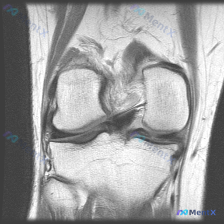

看到这张膝关节MRI冠状位T2加权图像,针对半月板异常的问题,整理了完整的读片分析思路,分享给大家一起讨论。 一、基本影像信息 这是一张膝关节MRI冠状位T2加权图像,先给大家整理系统性的解剖评估结果: 1. 骨骼关节:股骨远端、胫骨近端骨皮质连续,外侧胫股关节间隙大致正常,内侧胫股关节间隙无明显骨...

看到一份很有警示意义的膝关节MRI影像资料,整理出来和大家分享一下思路,这个病例很容易只看表面漏了关键问题。 病例基本影像信息 这是一张膝关节MRI冠状位T2加权成像,核心发现整理如下: 1. 骨骼:胫骨外侧平台区域可见明显局灶性高信号水肿影,提示骨挫伤/骨髓水肿,股骨远端骨皮质形态尚可,需排查隐匿...